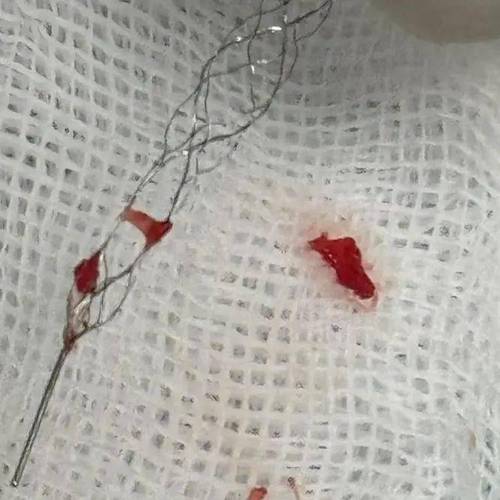

急性期取栓支架:

- 目的:在脑梗发生的急性期(通常6-24小时内),用于开通被血栓堵塞的大血管。

- 原理:医生通过导管将支架-like 的取栓装置送到血栓位置,抓住血栓并将其拉出体外,恢复血流。

- 瑞金医院:在这方面技术非常成熟,是上海乃至全国的卒中救治中心之一,能高效处理大血管闭塞。